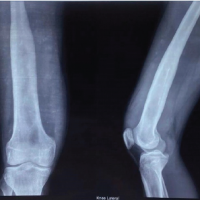

An 85-year-old female visited our hospital complaining of left knee pain. She had undergone ORIF with tension band wiring (TBW) for a left patellar fracture 7 months previously at a different hospital. However, bone union of the patellar fracture had not been achieved and the left knee pain persisted. She had a history of right patellar fracture and fractures of both ankles. Her body mass index was 25.6 kg/m2 (height, 157 cm; weight, 63.0 kg). Because of the left knee pain, she needed support for walking indoors and used a wheelchair outdoors. On physical examination, the range of motion (ROM) of the left knee was 0–120°. The pain was present at the medial joint space and around the patella, where it was particularly severe, with a Numerical Rating Scale (NRS; 0–10) of 8. Both of these areas were tender on palpation. No ligamentous instability was observed. Her Knee Society (KS) knee score was 53, and her KS function score was 40. Bone mineral density of the lumbar spine and proximal femur were 1.305 g/cm² and 0.678 g/cm², respectively. Radiographs of the left knee showed non-union of the patellar fracture, no joint space at the patellofemoral or medial femorotibial joints, and evidence of OA at the level of Kellgren–Lawrence classification stage IV at both of these sites (Fig. 1). Computed tomography (CT) of the left knee also showed non-union at the middle of the patella (Fig. 2). The femorotibial angle was 179°. There was no obvious implant failure of TBW. The diagnosis was severe knee OA with patellar non-union after a previous ORIF. As treatment for the patellar non-union and bone fragility, we initially treated the patient with low-intensity pulsed ultrasound (LIPUS) (Exogen Ultrasound Bone Healing System; Bioventus, Durham, NC) and teriparatide injection (Teribone; Asahi Kasei Pharma, Tokyo, Japan). LIPUS (1.5 MHz) was applied to the affected area for 15 min every day. As there was insufficient improvement in both the subjective symptoms and imaging findings in the left knee after 1 year of treatment, we decided to perform TKA and surgery for non-union of the patella in a one-stage procedure.